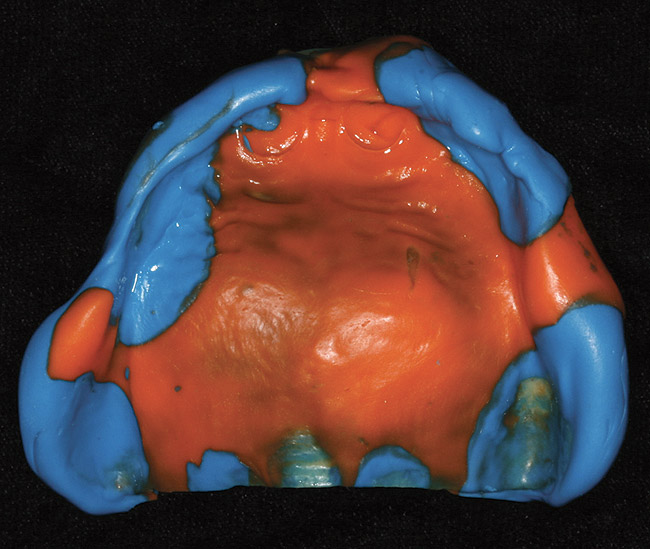

Figure 7  Maxillary final impression made with vinyl poly siloxane material in a custom tray.

Figure 7

Figure 8  Mandibular final impression made with vinyl poly siloxane material in a custom tray.

Figure 8